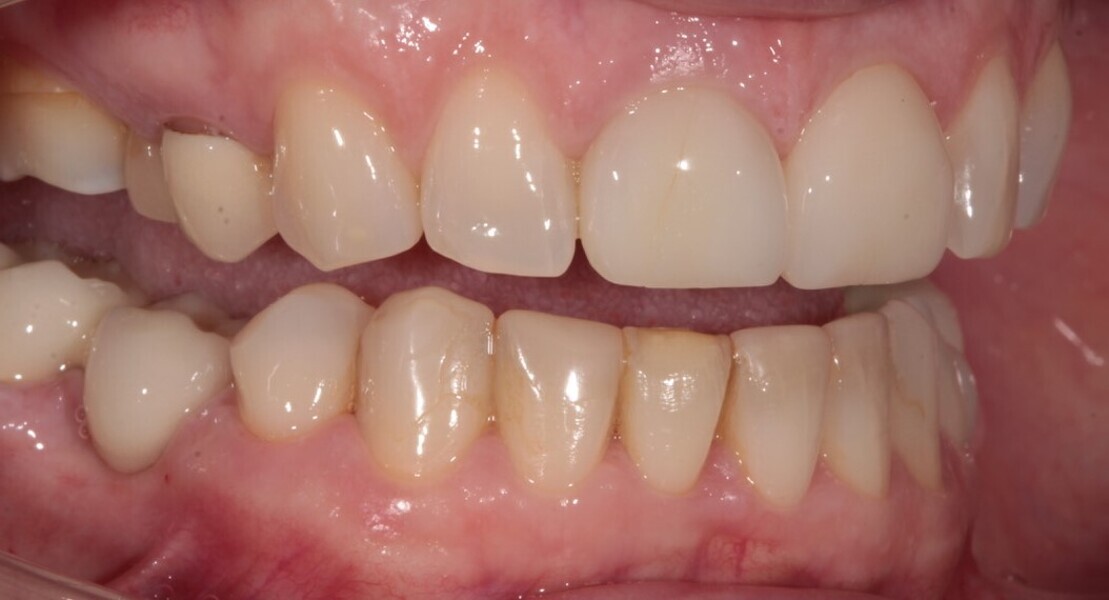

A 48-year-old female patient came to see me in 2004. The patient initially presented because she was unhappy with her two discoloured maxillary central incisors (Fig. 1). She also had chipping and wear of the mandibular teeth and broken posterior bridgework. Her “bite” also felt uncomfortable (Fig. 2).

On examination, she had reduced anterior guidance, causing posterior interferences and heavy contacts behind the maxillary central incisors. The patient was keen to change the crown and veneer on the maxillary central incisors. She also wanted to have the wear on her mandibular teeth and the crowding treated (Fig. 3).

Fig. 2: 2004—reduced anterior guidance.